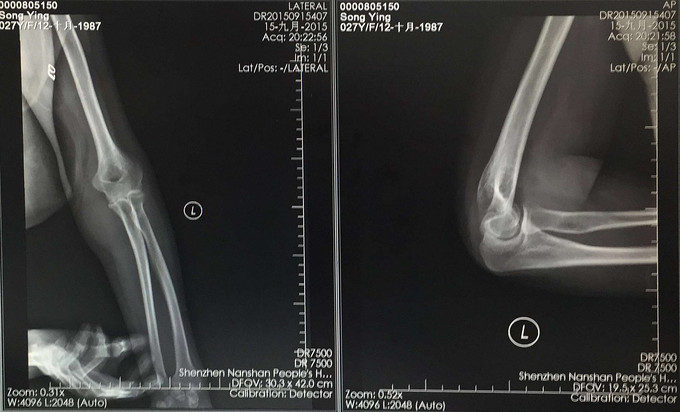

患者术后5天出院,术后2周功能恢复满意。